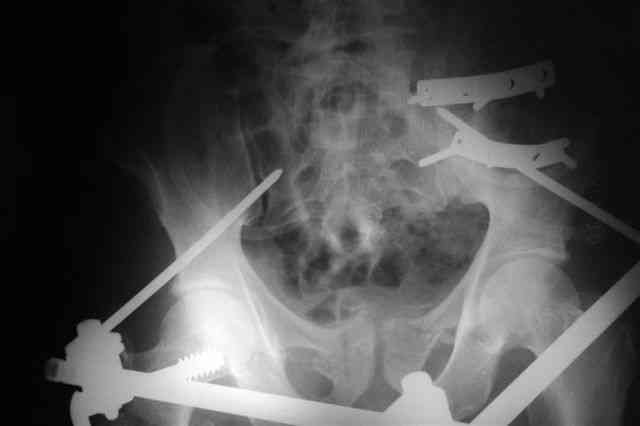

В приложении послеоперационные картинки.

При поступлении передняя рама (фиксация просто за гребни), соединенная с мыщелками бедра.

После стабилизации состояния перевернуть больного на живот или на бок, пару винтов закрыто через заднюю ость трансфрактурно в крыло слева (если не нравится стояние фрагмента, можно предворительно задним латеральным доступом отрепонировать), справа не очень понятно куда идет перелом крыла, но если фиксировать, то пластиной по наружной стороне.

Интраоперационно у меня не возникло сомнений , что Шанцы прошли через КП сочленения: сначала провёл Шанц справа при открытой ране после фиксации КП

сочленения пластинами и контролем ЭОПа инлет и аутлет проекциях, определившись с углом введения винта. затем слева - под Рг-контролем, отступив на 2 см латеральнее нижней ости, чтобы не провалиться в таз.

На следующий день больной активизирован с костылями, на боли не жаловался,

поэтому и не стал заказывать томографию, хотя, для протокола надо было бы.